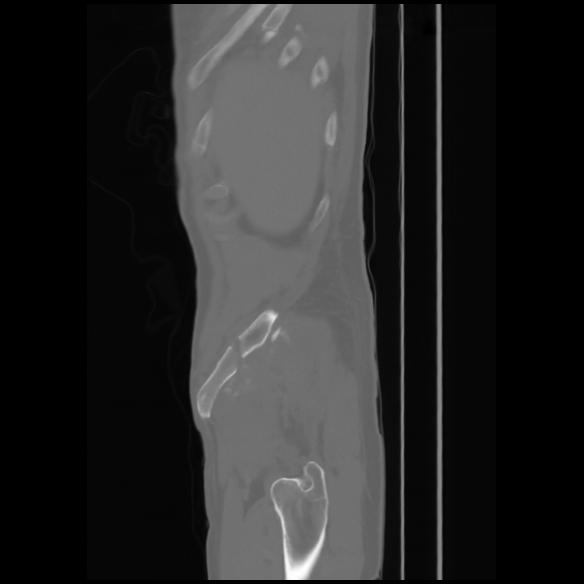

7 CUERPO,CE,Sagittal,3.000,CUERPO,Sagittal,